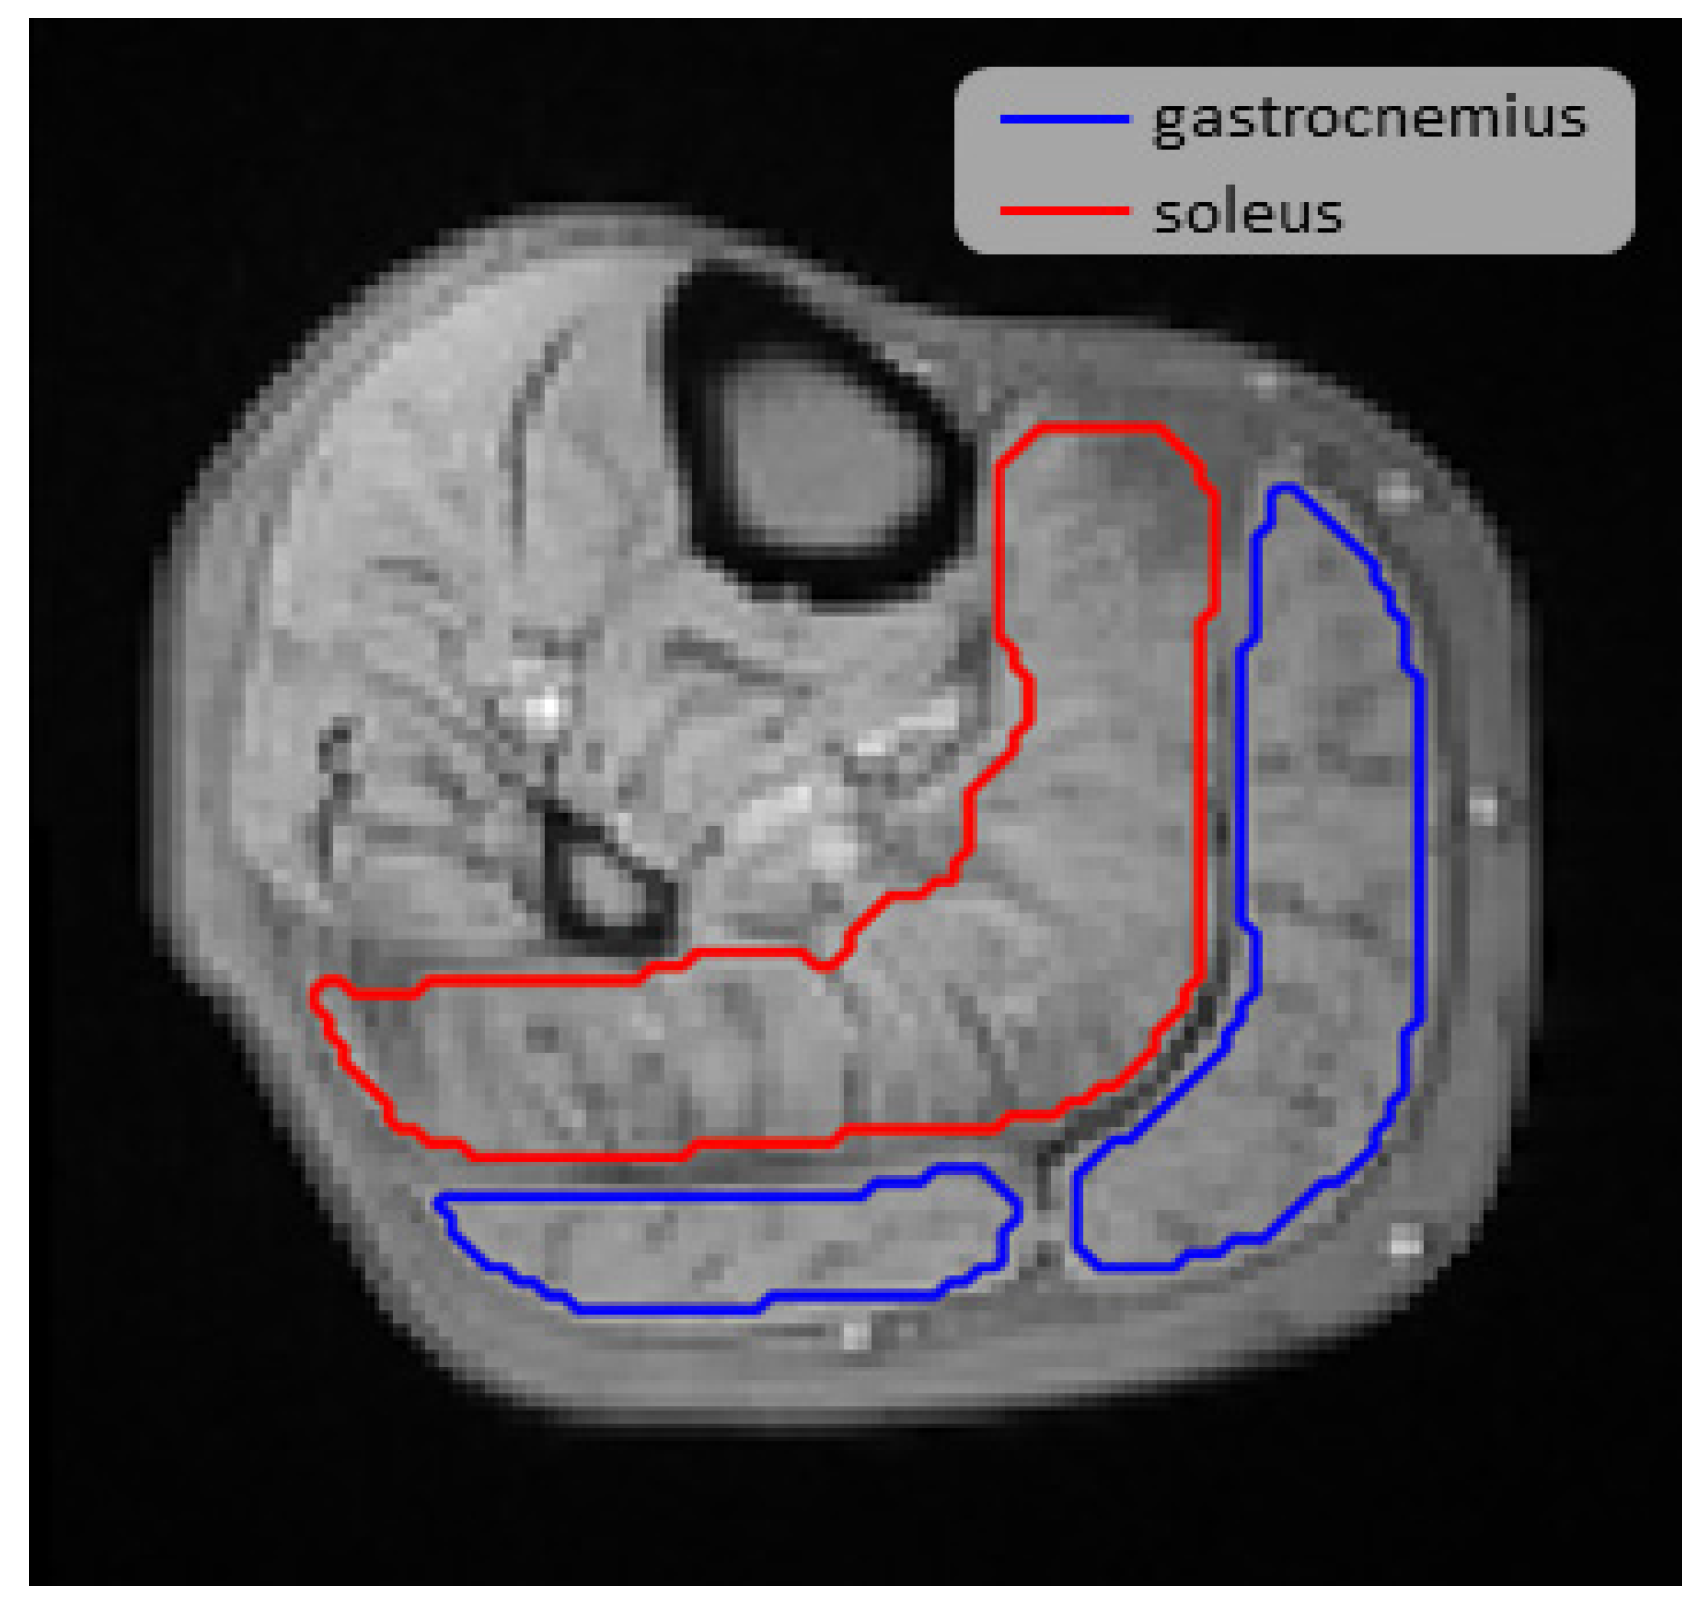

2.3. Image Post Processing

| BL (ms) gastrocnemius | 25.3 ± 2.9 | 24.6 ± 4.1 | 0.59 |

| BL (ms) soleus | 21.2 ± 2.8 | 20.8 ± 3.9 | 0.91 |

| HPV (ms) gastrocnemius | 25.8 ± 2.5 | 26.1 ± 4.3 | 0.31 |

| HPV (ms) soleus | 22.8 ± 2.7 | 22.6 ± 4.3 | 0.96 |

| TTP (s) gastrocnemius | 111 ± 46 | 48 ± 22 | <0.01 |

| TTP (s) soleus | 100 ± 42 | 41 ± 30 | <0.01 |

| Overshoot (ms) gastrocnemius | 0.59 ± 0.93 | 1.49 ± 1.22 | 0.03 |

| Overshoot (ms) soleus | 1.59 ± 0.96 | 1.81 ± 1.86 | 0.46 |